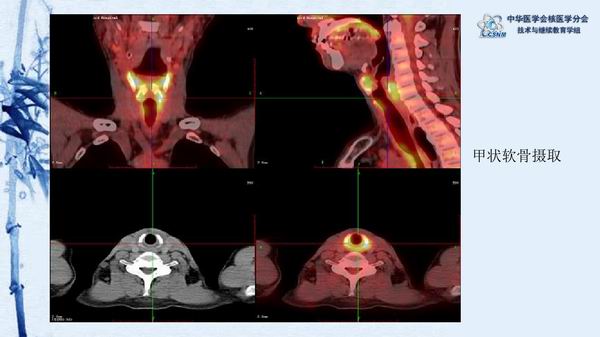

讲座15:复发性多软骨炎-张卫方